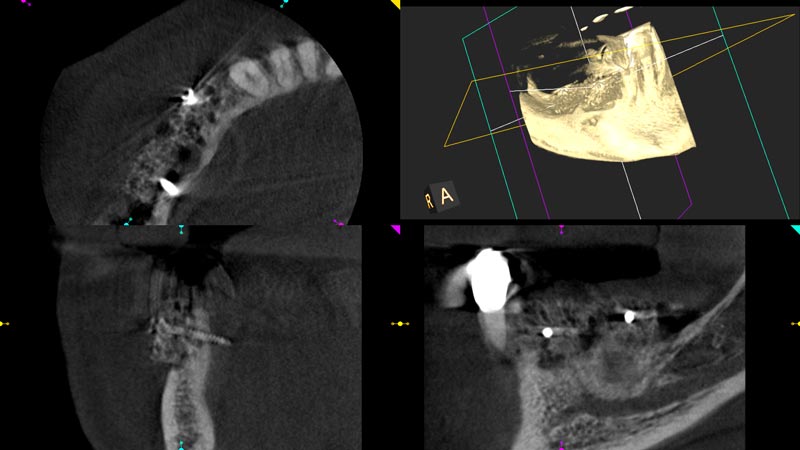

03/14 - Initial CBCT scan showing severe ridge atrophy in the right mandible

Block augmentation with maxgraft® in the mandible - PD Dr. Dr. F. Kloss